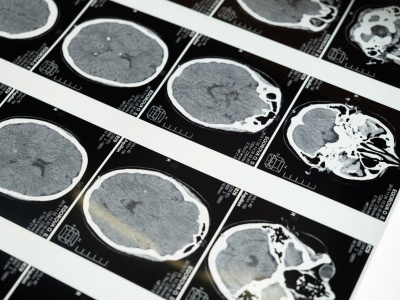

Badania pokazują, że menopauza zmienia strukturę mózgu kobiety – wpływa na pamięć, koncentrację i emocje. Jakie procesy za tym stoją? Artykuł Jak menopauza wpływa na strukturę i funkcje mózgu? Najnowsze badania 2025 pochodzi z serwisu Alert Medyczny.